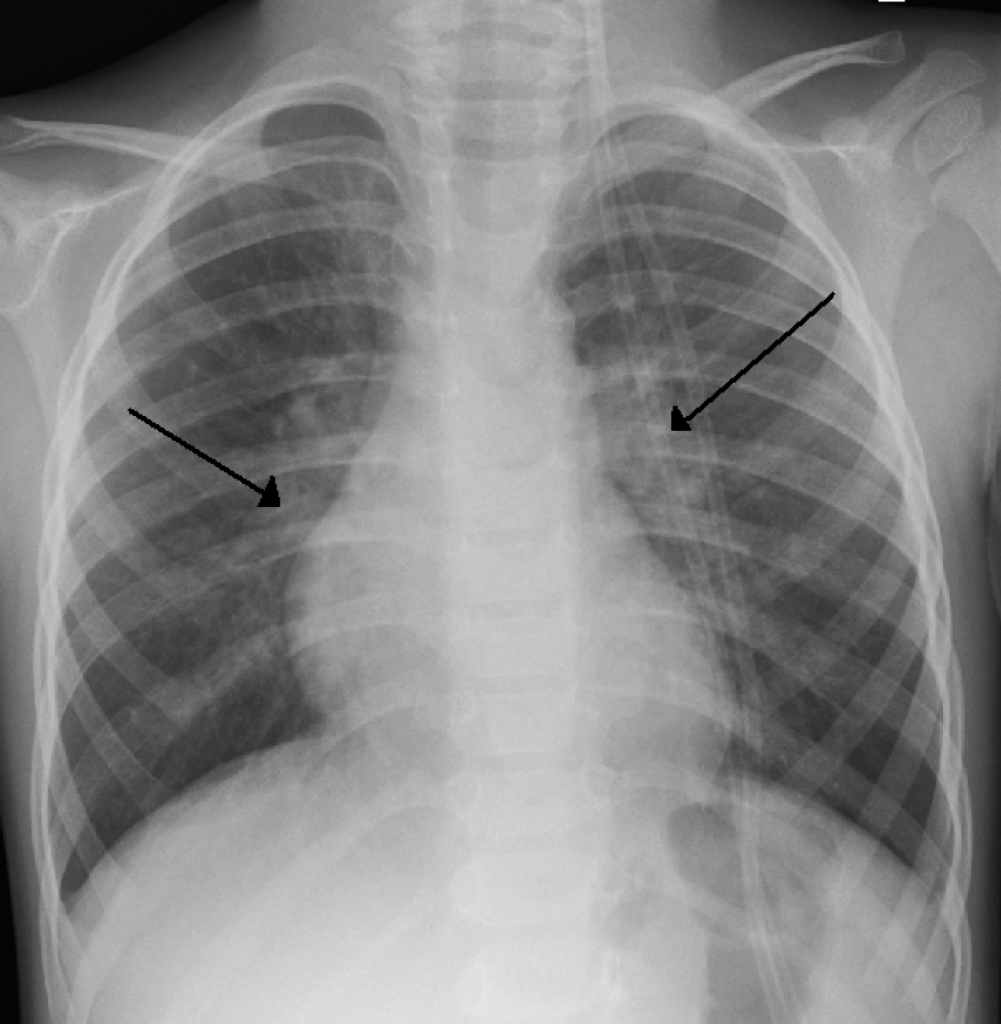

Dans ce contexte, la priorité doit donc être d’éviter la contamination des nourrissons, chez qui le symptôme le plus fréquent, la toux, peut se traduire par une respiration plus rapide et sifflante, parfois accompagnée de fièvre et de difficultés à manger et à dormir. Si un traitement prophylactique existe – l’injection d’un anticorps monoclonal, le palivizumab, commercialisé sous le nom de Synagis –, aucun vaccin n’est pour le moment disponible. La prévention repose donc principalement sur des mesures d’hygiène, comme se laver les mains avant et après avoir touché un nourrisson, éviter d’emmener son enfant dans des lieux publics confinés, aérer les pièces et nettoyer les objets avec lesquels il est souvent en contact. Des mesures proches de celles appliquées contre le Covid-19.